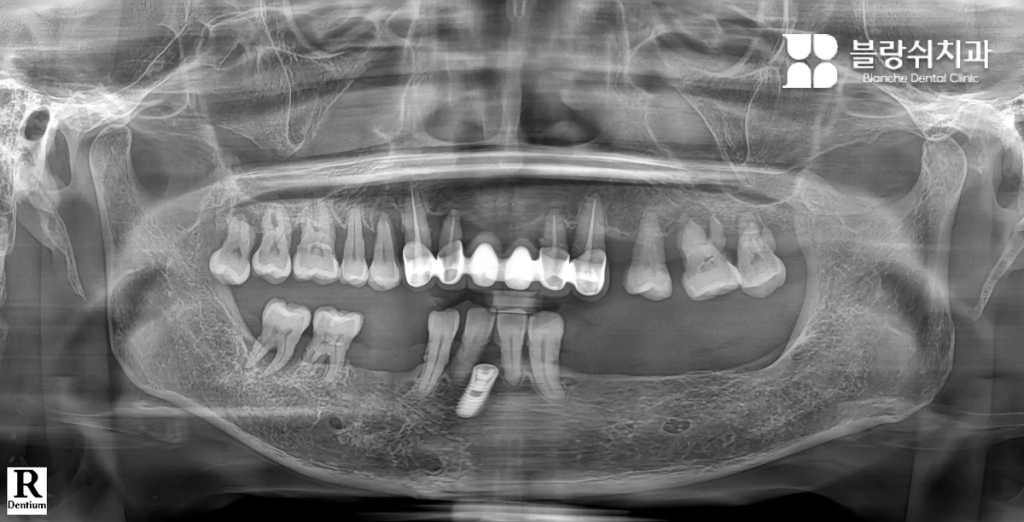

Case 1. 틀니와 장기 치료가 부담이었던 50대 남성

이 환자분은 여러 개의 치아 손상과 잇몸 약화로 인해 정상적인 저작이 어려운 상태였습니다. 전통적인 전체 임플란트를 고려했지만, 수개월에서 1년 이상 소요되는 치료 기간잇몸 절개 수술에 대한 부담으로 치료를 망설이고 계셨습니다. 특히 “잇몸을 크게 절개해야 한다”는 점이 가장 큰 두려움이었습니다.

• 디지털 풀아치 임플란트를 선택한 이유 인터넷 검색을 통해 디지털 풀아치 임플란트를 알게 되었고, 짧은 치료 기간과 최소 절개 수술이라는 점에 관심을 갖고 내원하셨습니다. 상담 과정에서 3D CT와 디지털 스캐닝을 통해 구강 상태를 정밀 분석했고, 임플란트 개수를 최소화하면서도 전체 치아 기능을 회복할 수 있는 구조라는 설명을 듣고 치료를 결정하셨습니다.

• 치료 후 변화 “이제는 음식 종류를 가리지 않고 먹을 수 있어서 삶의 만족도가 확실히 달라졌습니다.” 디지털 스캔 데이터를 기반으로 3D 치료 계획을 수립한 뒤, 컴퓨터 가이드 수술로 임플란트를 정확한 위치에 식립했습니다. 이후 CAD/CAM 기술로 제작된 풀아치 보철물을 장착하며 치료가 진행되었고, 적은 방문 횟수로 치료를 마칠 수 있었습니다.